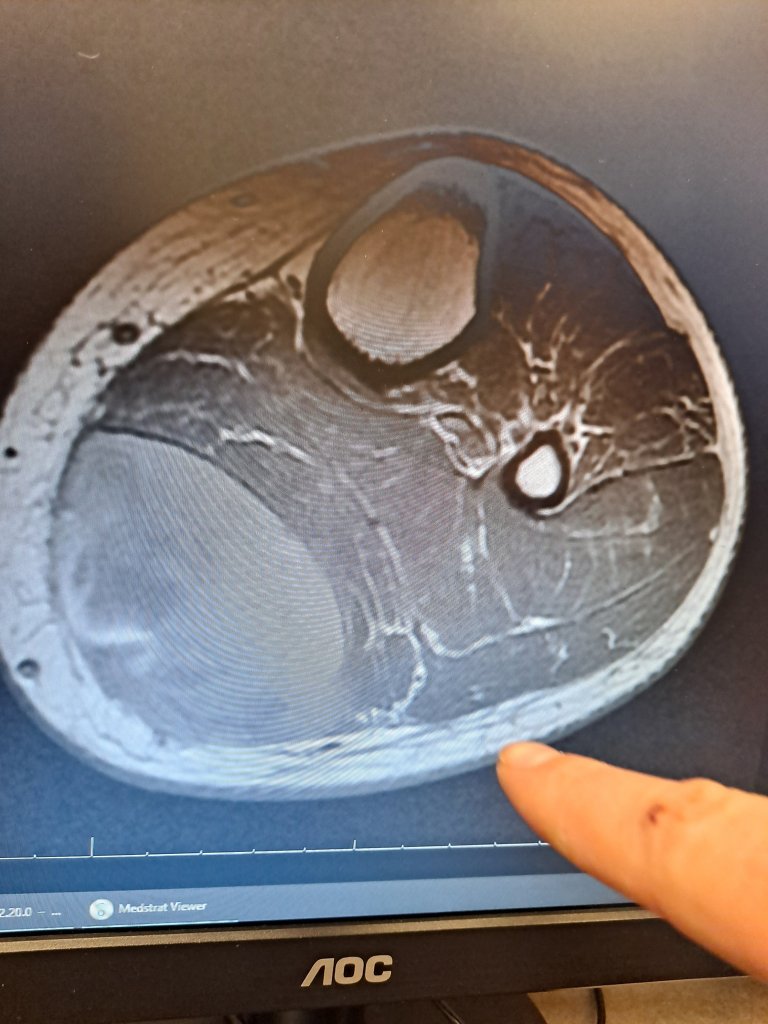

I got another doppler ultrasound, bloodwork, and two MRI’s that showed a huge pocket of blood pressing on my calf.

They drained off some fluid and blood, and released enough pressure I could finally put my foot down, (it continued to leak out for 2 more days) but I still cannot straighten my knee. It’s a ruptured bakers cyst caused by a torn meniscus and severe osteoarthritis.